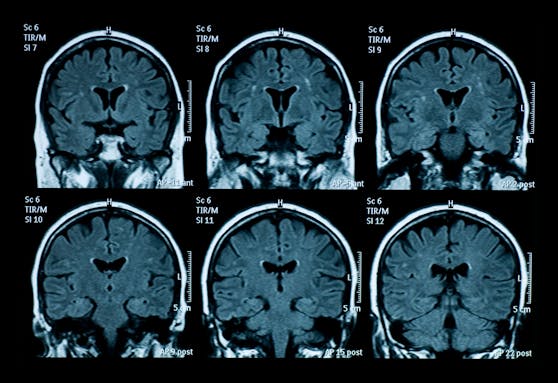

Eine neue Studie aus England zeigt, dass eine Covid-Infektion das Hirn schrumpfen lassen kann. Betroffen sind vor allem die Hirnareale für kognitive Fähigkeiten. Diese Long-Covid-Symptome sind nicht nur bei schweren Verläufen, sondern auch bei "milden" Verläufen möglich, so die Studie. Die Gehirne der Betroffenen wurden zwischen März 2020 und April 2021 untersucht.

So gäbe es bis dato zum Beispiel keine konkreten Hinweise dafür, dass die aktuell dominanten Omikron-Varianten BA.1 und BA.2 oft zu Hirnschäden führen würden. Zudem habe die britische Studie sich hauptsächlich mit der Morphologie, also mit der Form und Struktur des Gehirns, befasst. "Was man auf den Bildern sieht und was effektiv im Hirn abgeht, sind zwei verschiedene Paar Schuhe", sagt Cerny.